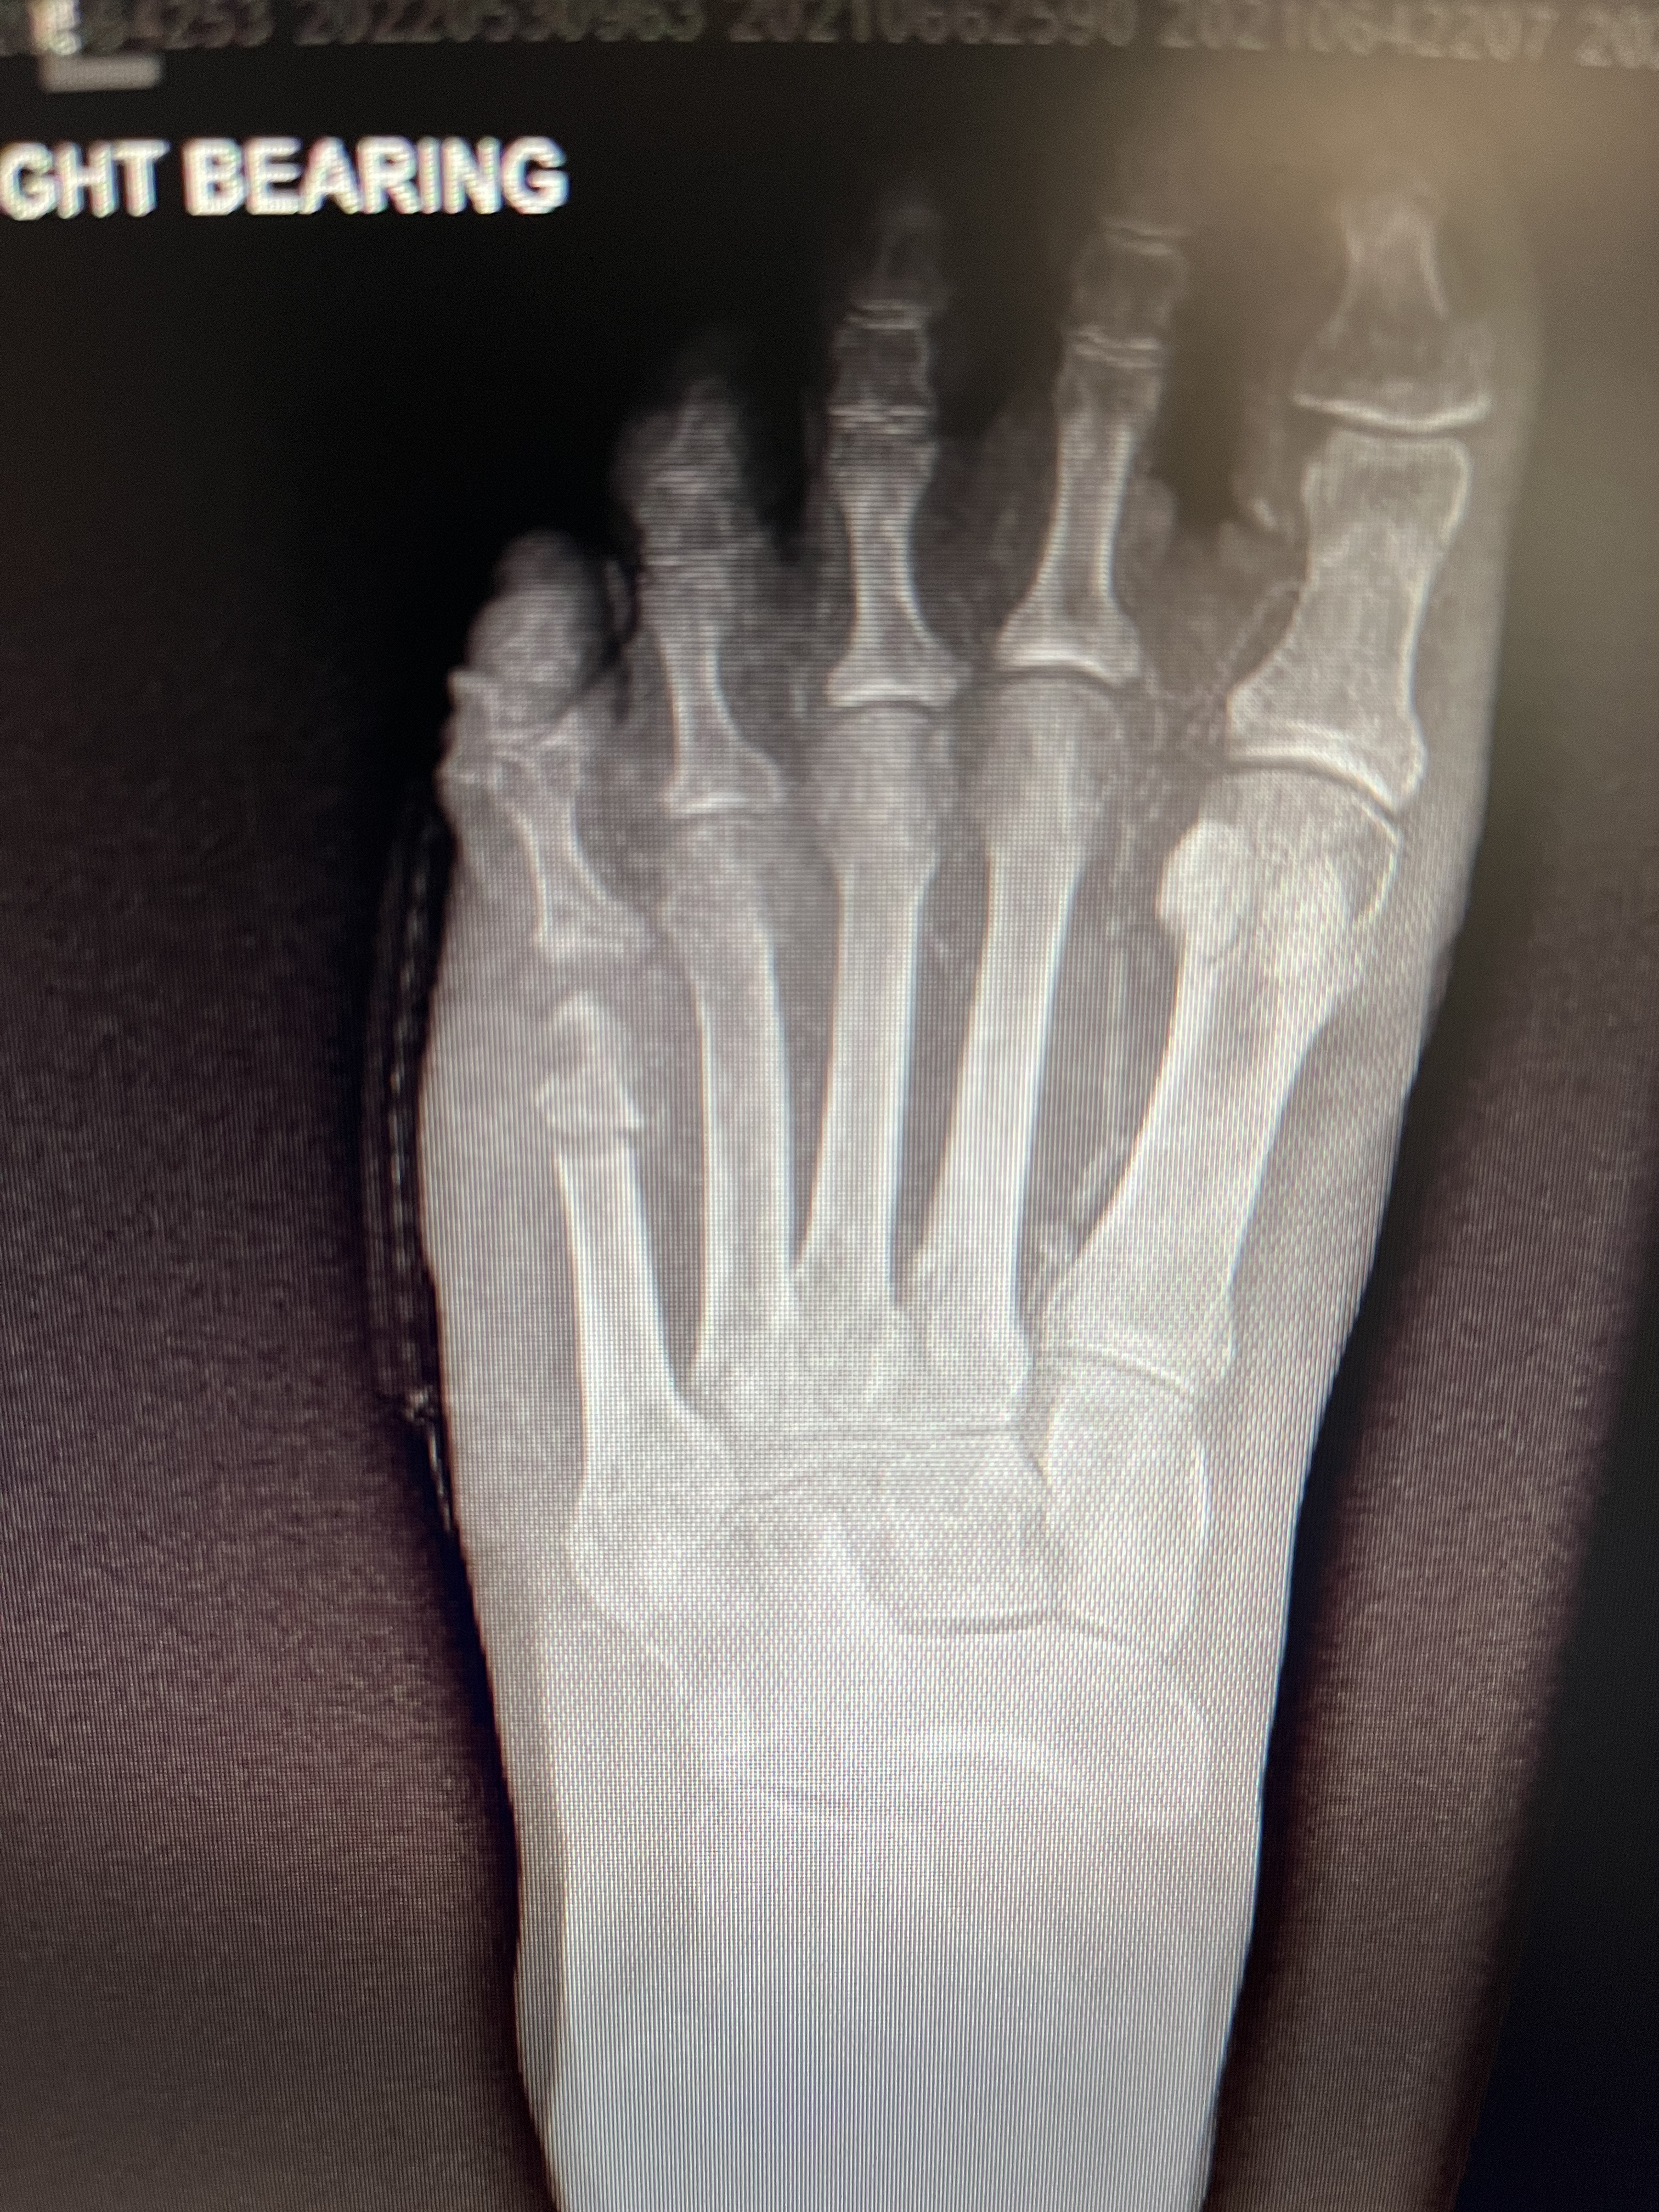

2) גישה זעיר פולשנית (Minimally invasive floating metatarsal osteotomy) - בגישה הזאת החתך הניתוחי הוא פחות מ1 ס״מ. יוצרים ״שבר״ בצוואר המסרק ונותנים לו ״לצוף״ למעלה כדי להוריד מהלחץ ולסגור את הפצע. מכיוון שהמטופלת היא סכרתית ויש לה נורפטיה (חוסר תחושה עצבית), היא לא תרגיש כאב מה״שבר״ ואין חשש לגבי אם השבר יתאחה או לא.

- מכיוון שהחתך הניתוחי מאוד קטן, זמן ההחלמה הוא מינימלי והמטופל יכול לדרוך וללכת כבר ביום הניתוח.

כמובן שבחרנו בגישה הזעיר פולשנית. בצילום אפשר לראות איפה היה החיתוך של העצם. בנוסף, ניתן לראות כיצד חלק מהעצם כבר ״נאכלה״ על ידי הזיהום. ברגע שהעצם נחתכה והפצע החלים, הסיכוי שהזיהום יתפשט ויחמיר הוא מאוד נמוך.